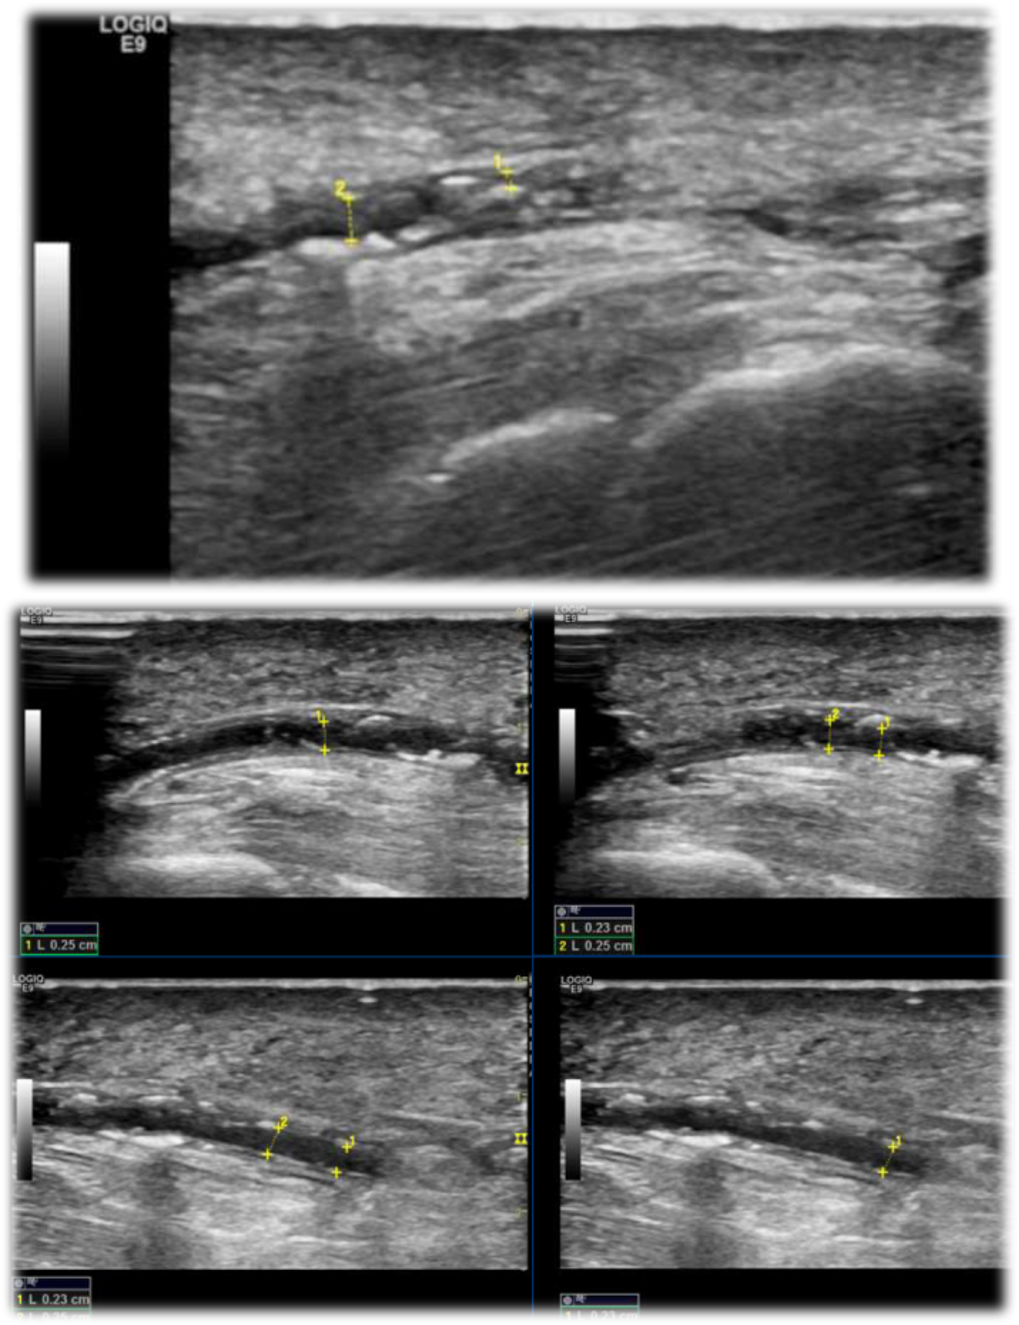

可视化工具:透视/DSA(评估钙化范围)、超声(检测钙化厚度)、足部 X 线(侧位 + 前后位,观察 “rail-tracking” 钙化长度);

超声